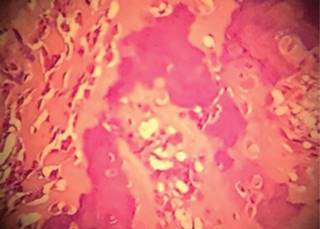

Se realizó la biopsia transquirúrgica, la cual reveló abundante tejido fibroconectivo con osteoblastos y nidos de hueso trabecular con matriz ósea y tejido osteoide e hipervascularidad del estroma, aumento de la celularidad sin atipias y escasas células gigantes multinucleadas (Figura 4); se clasificó como Enneking 2. Se inició tratamiento con resección y curetaje del tumor, crioterapia y colocación de injerto tricortical en el defecto en cuboides (Figura 5).

Figura 4: Resultado histopatológico microscópico.